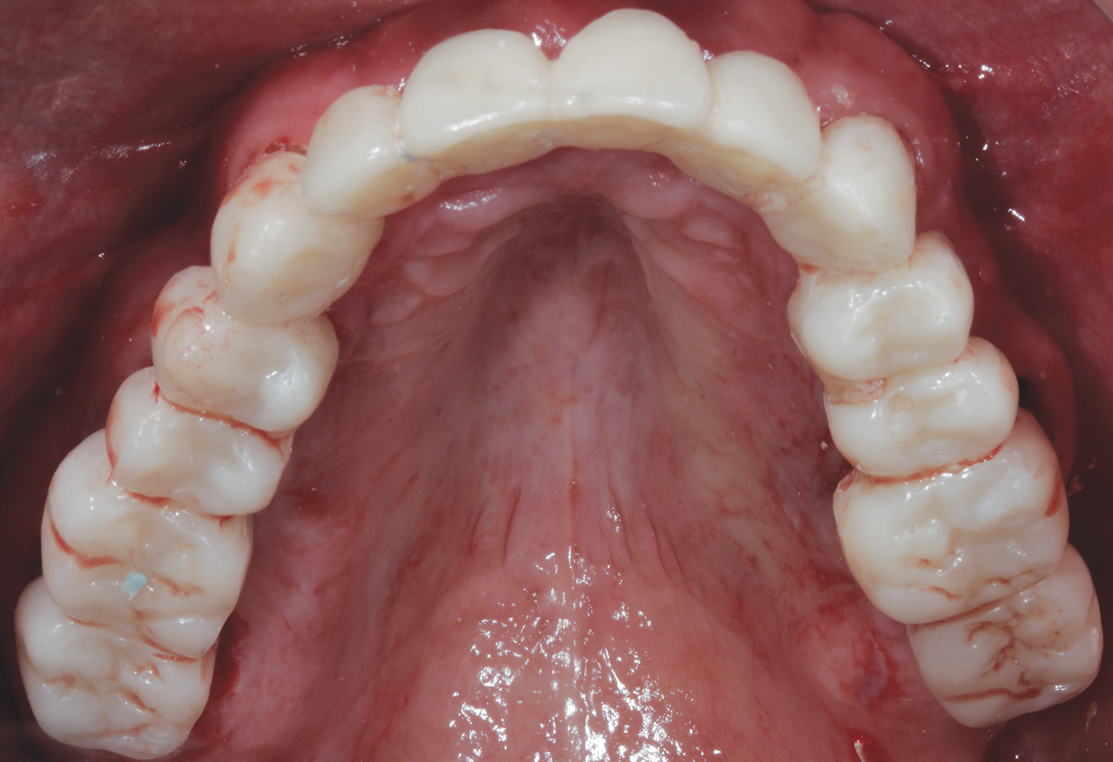

The dental technician can duplicate the same emergence obtained with the provisional for the final prosthesis (Figure 23).